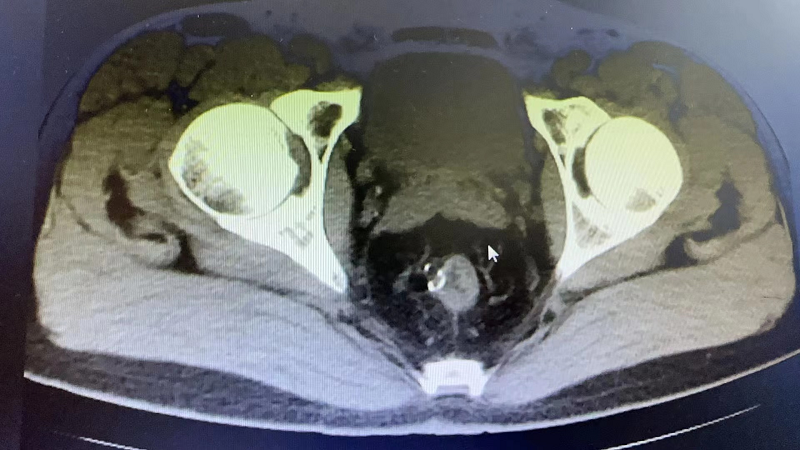

数月前,禾禾刚过完9岁的生日,她是个懂事乖巧的小姑娘,学习成绩也十分优秀,一家人其乐融融。可原本温馨的家庭氛围戛然而止,禾禾突然开始变得不爱说话,甚至有时候会冲人大喊大叫,家人怀疑禾禾是青春期的心理问题,一直耐心疏导,可更可怕的事情出现了。突然有一天,禾禾毫无征兆地开始抽搐,慢慢神志不清,胡言乱语,甚至不能行走。家人慌了神,着急地带着禾禾赶到八院,进入抢救室后禾禾出现了一侧肢体持续抽搐伴扭动,儿科急诊医生立刻通知了谢国栋副主任和彭晨娜医生,通过对父母询问病史以及了解治疗情况,分析孩子发病的整个过程,医生怀疑她罹患的是“自身免疫性脑炎”。收住入院当天禾禾完成了腰穿送检,2天后的血样和脑脊液送检结果明确诊断:抗NMDAR脑炎。

针对禾禾的病情,儿科主任高燕敏多次组织医护团队开展病情讨论和分析,决定对禾禾给予一线免疫治疗,同时加强专业护理。但是因为禾禾病情危重,治疗难度较大,日常护理也成了一个大问题,禾禾需要24小时看护。在医护人员和家人的团结一心下,经过3周的规范免疫治疗,禾禾的一侧肢体抽搐以及其他相关症状明显缓解。